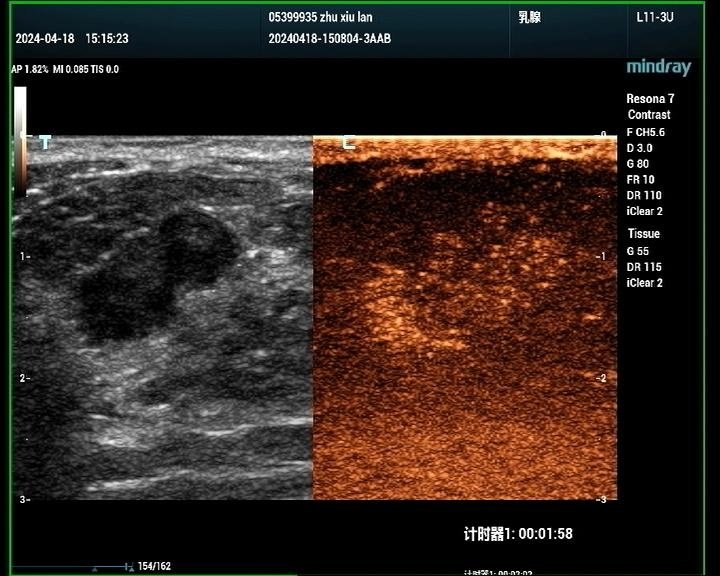

2、乳腺

判断肿瘤的良恶性:通过超声造影,医生可以初步判断乳腺肿瘤的良恶性,为临床治疗提供参考。

明确恶性肿瘤的范围:对于恶性肿瘤,超声造影能够明确其范围,有助于制定手术方案及评估预后。

术后瘢痕与肿瘤的鉴别:乳腺手术后的瘢痕与肿瘤在超声表现上可能存在相似性,超声造影有助于二者的鉴别。

非手术治疗疗效评估:对于非手术治疗的乳腺癌患者,超声造影能够评估其疗效,为治疗方案的调整提供依据。

乳腺癌病例